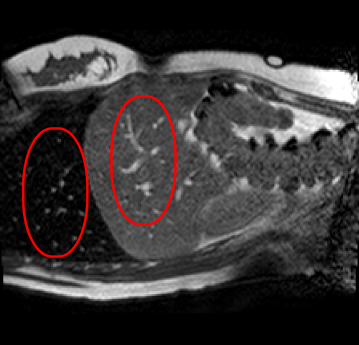

With this motivation, [6] proposed a convolutional neural network (CNN) based approach for temporal interpolation of navigators. Their CNN takes as inputs a fixed number of acquired images and learns to predict the missing images directly in the intensity space. This approach, which we call the Simple Convolutional Interpolation Network (SCIN), is a ’black-box’ formulation that does not incorporate any prior information about the interpolation process. Image prediction is guided only by the cost function used to optimize the network parameters. The issue with this is that it is unclear whether the image similarity measures that are generally used as cost functions suffice to ensure fidelity of the generated images to the original images. Indeed, Fig. 1b shows a case where an image interpolated using SCIN is quite blurry and misses several liver and lung structures present in the original image.

(a)                                (b)                                (c)

Figure 1: (a) Ground truth and (b,c) interpolated images from (b) baseline (SCIN) and (c) proposed method (MFIN). The image interpolated via SCIN is heavily blurred and misses several lung and liver structures, while the proposed method is able to preserve the details in the ground truth image.